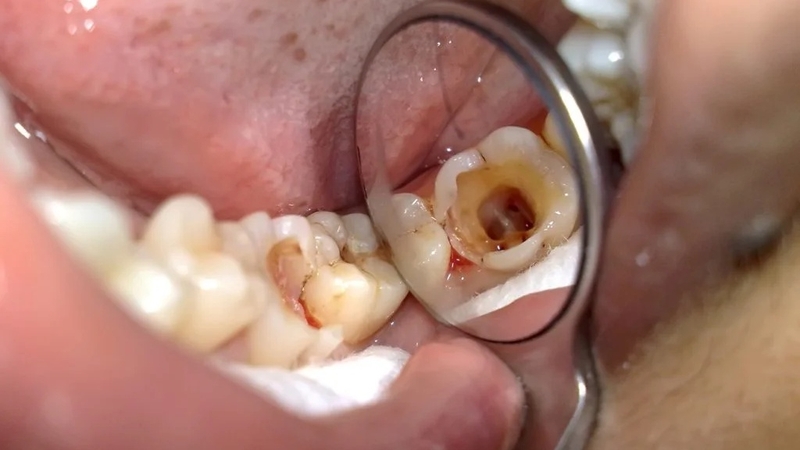

Tuy nhiên, trong trường hợp răng có dấu hiệu viêm nhiễm như sâu răng gây đau nhức, mô răng bị hư vỡ, chấn thương làm lộ tủy, hoặc răng có nguy cơ bị nhiễm trùng, việc lấy tủy là cần thiết. Bác sĩ sẽ tiến hành kiểm tra và chụp phim để xác định mức độ tổn thương chính xác.

Nếu tổn thương răng ở mức nghiêm trọng, dây thần kinh trong tủy đã tổn thương trầm trọng và không thể giữ lại tủy, bác sĩ sẽ quyết định lấy tủy trước khi tiến hành trám răng. Theo đó, tủy răng được lấy ra, vùng rỗng bên trong răng sẽ được sát trùng và trám bít lại.